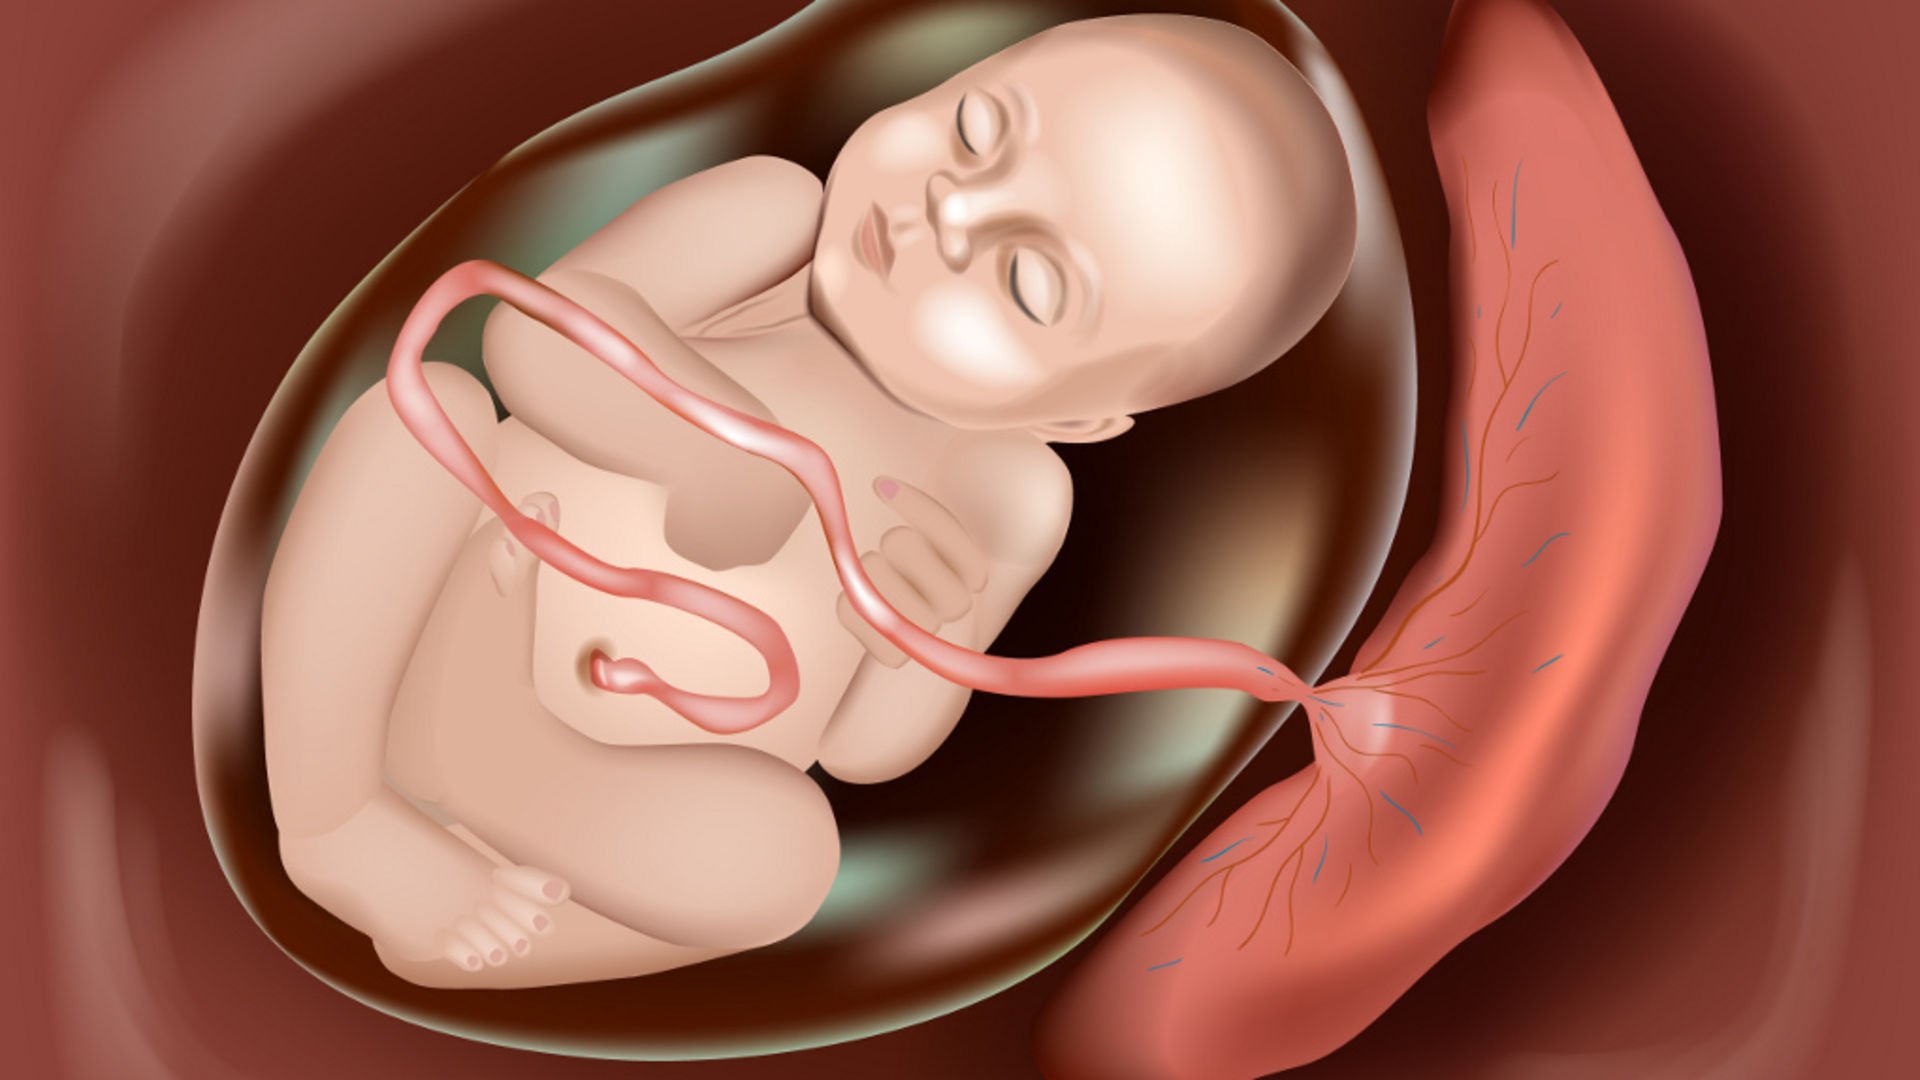

Расположение ребенка и пуповины

Ребенок в утробе с пуповиной

Внутриутробный плод и плацента